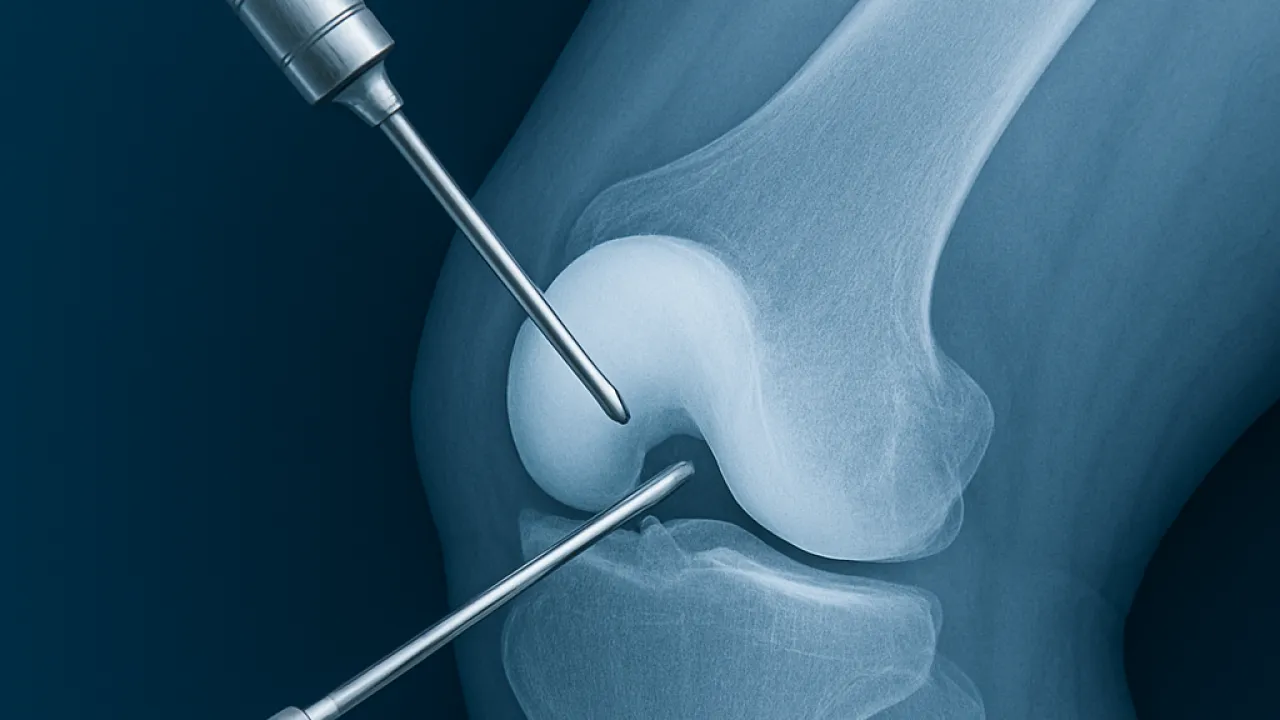

Artroskopik cerrahi, halk arasında “kapalı eklem ameliyatı” olarak bilinir. Küçük kesilerden ekleme yerleştirilen kamera ve özel aletler sayesinde eklemin içi net bir şekilde görülür ve sorunlu yapılar tedavi edilir. Bu yöntem sayesinde hem teşhis hem de tedavi aynı seansta yapılabilir.

Günümüzde artroskopik cerrahinin en sık uygulandığı eklemler **diz** ve **omuz** eklemleridir. Bunların dışında **ayak bileği, kalça, el bileği ve dirsek** eklemleri ile el ve ayaktaki küçük eklemlere de artroskopik girişim rahatlıkla uygulanabilir.

Dizde özellikle menisküs yaralanmalarında, ön ve arka çapraz bağ yırtıklarının onarımında, kıkırdak doku patolojilerinde, eklem içi iltihaplanmada ve orta dereceli diz eklemi kireçlenmesinde artroskopik girişimler uygulanmaktadır.